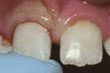

שן קדמית שבורה

שן שבורה לאחר תיקון